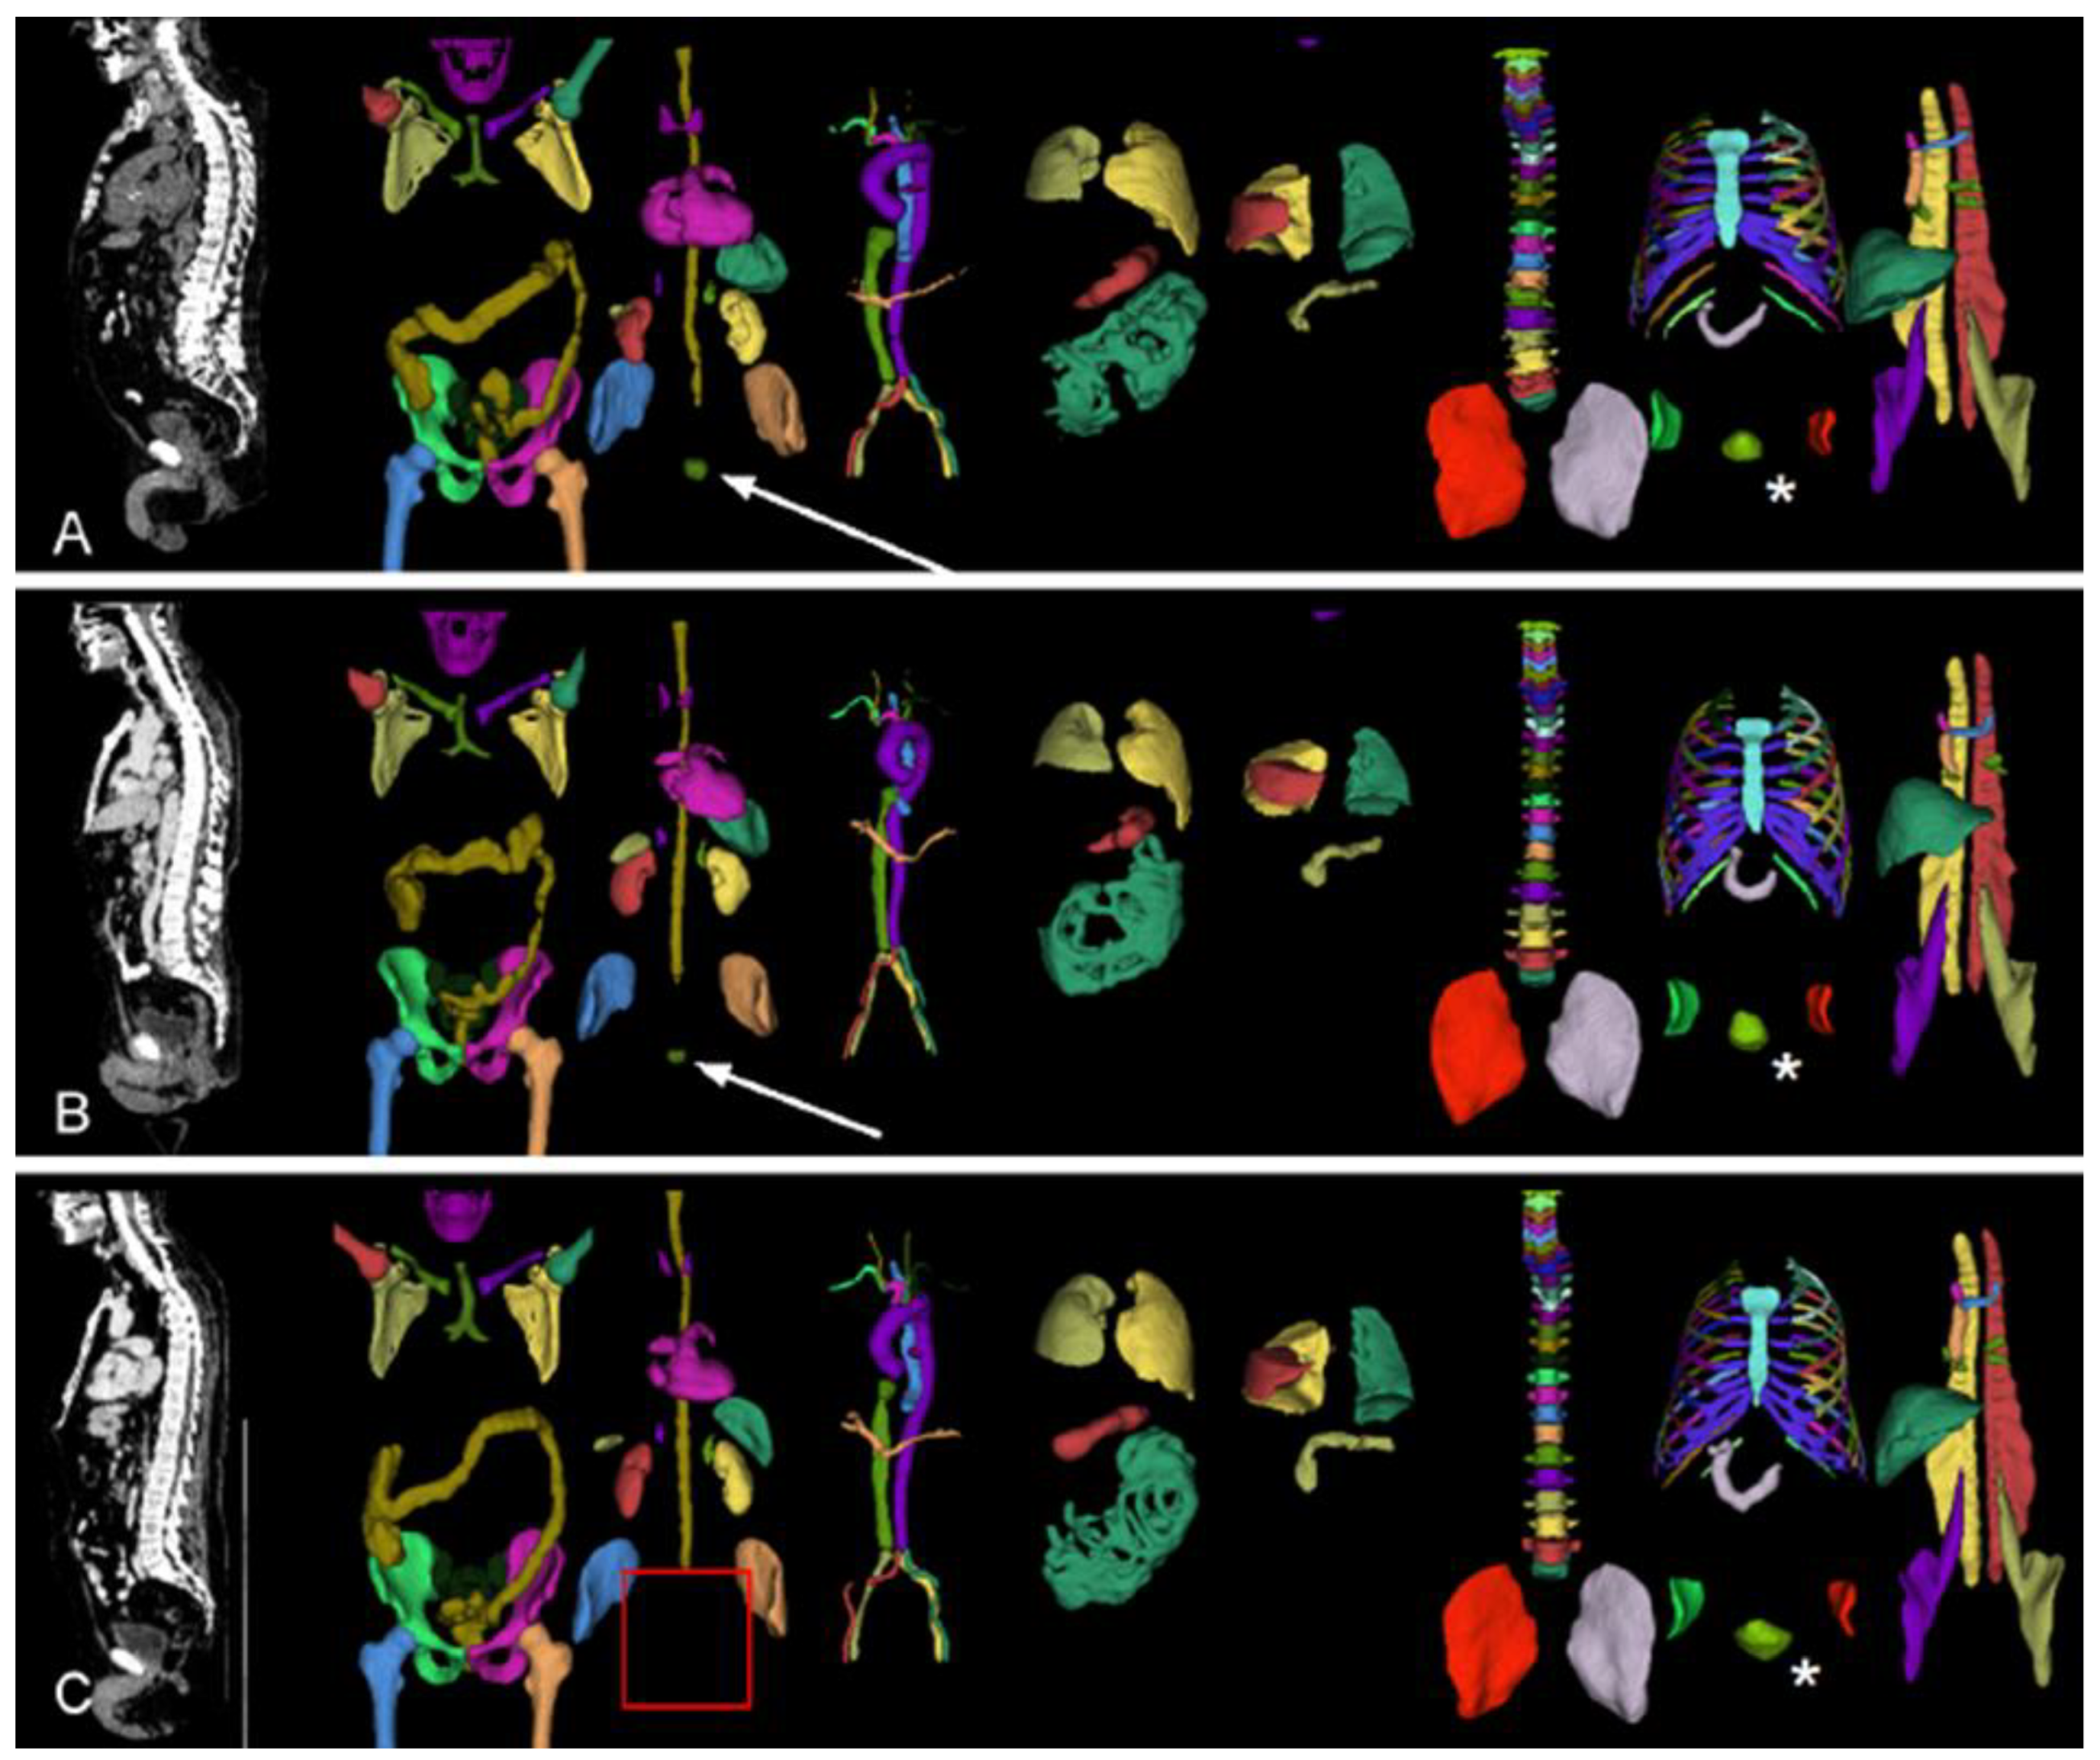

Figure 2. Result of TotalSegmentator [15] On three patients. White arrows indicate the detected prostate gland in patients A and B, while the red rectangle indicates the absence of the prostate gland in patient C. The white asterisks indicate that the urinary bladder was successfully detected in all patients.

The data includes the whole body, while the specific question (local recurrence) can be answered by focusing on the area around the prostate (region). To automatically crop image volumes around the prostate, the location of the prostate is determined by TotalSegmentator (version 2.1.0, [15]). This worked in most cases, even for patients after radical prostatectomy. In the remaining cases, the position of the urinary bladder was used as a proxy (Figure 2). Images were cropped to a 10cm x 10cm x 10cm cube around the centroid of the prostate (or urinary bladder) in patient coordinates and re-scaled to 70x70x70 voxels. Variants with stronger cropping have been explored (Appendix A).